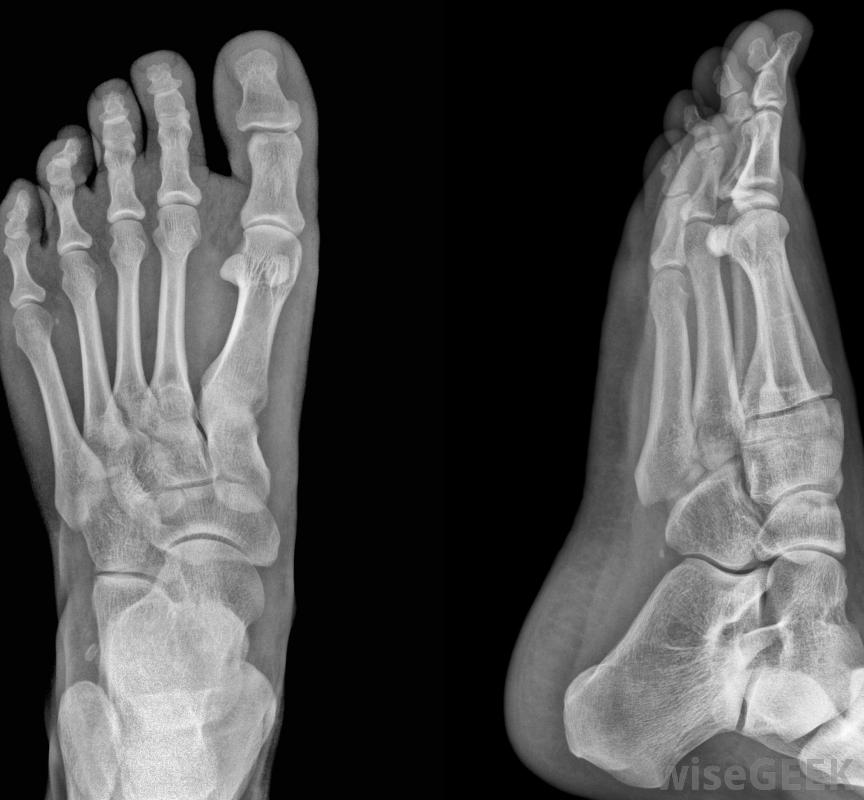

x光片可以用來檢查囊腫。